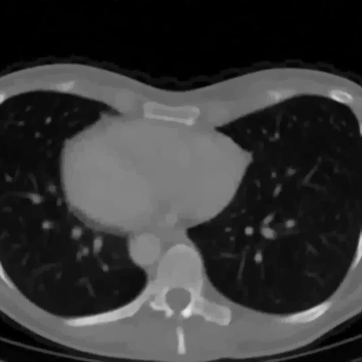

In Figure 12 we compare the PD3O reconstructions (top) and their corresponding errors with respect to the ground truth (bottom) using different regularization parameter choices , and for PD3O. Obviously, using the estimated parameter-map leads to a significant improvement of the reconstruction. In particular, sharp edges are retained, while using a constant regularizing parameter results in a significant blur. This can be also seen in Table 4, where we compare the NRMSE, PSNR, SSIM and blur and evaluated on the first 100 test images of the LoDoBaP dataset. These results are visualized in Figure 13 using box-plots. Note that the FBP seems to better than PD3O- in terms of the blur effect, but this can be explained by the fact that FBP reconstructions admit a lot of high-frequency artefacts leading to a small blur effect.

Further PD3O- reconstructions with their corresponding estimated parameter-maps are shown in Figure 14. Note that the parameter-maps are given in a logarithmic scale. As expected, the regularization is strong in constant areas and less strong on edges or finer details in order to reduce a smoothing in these regions.